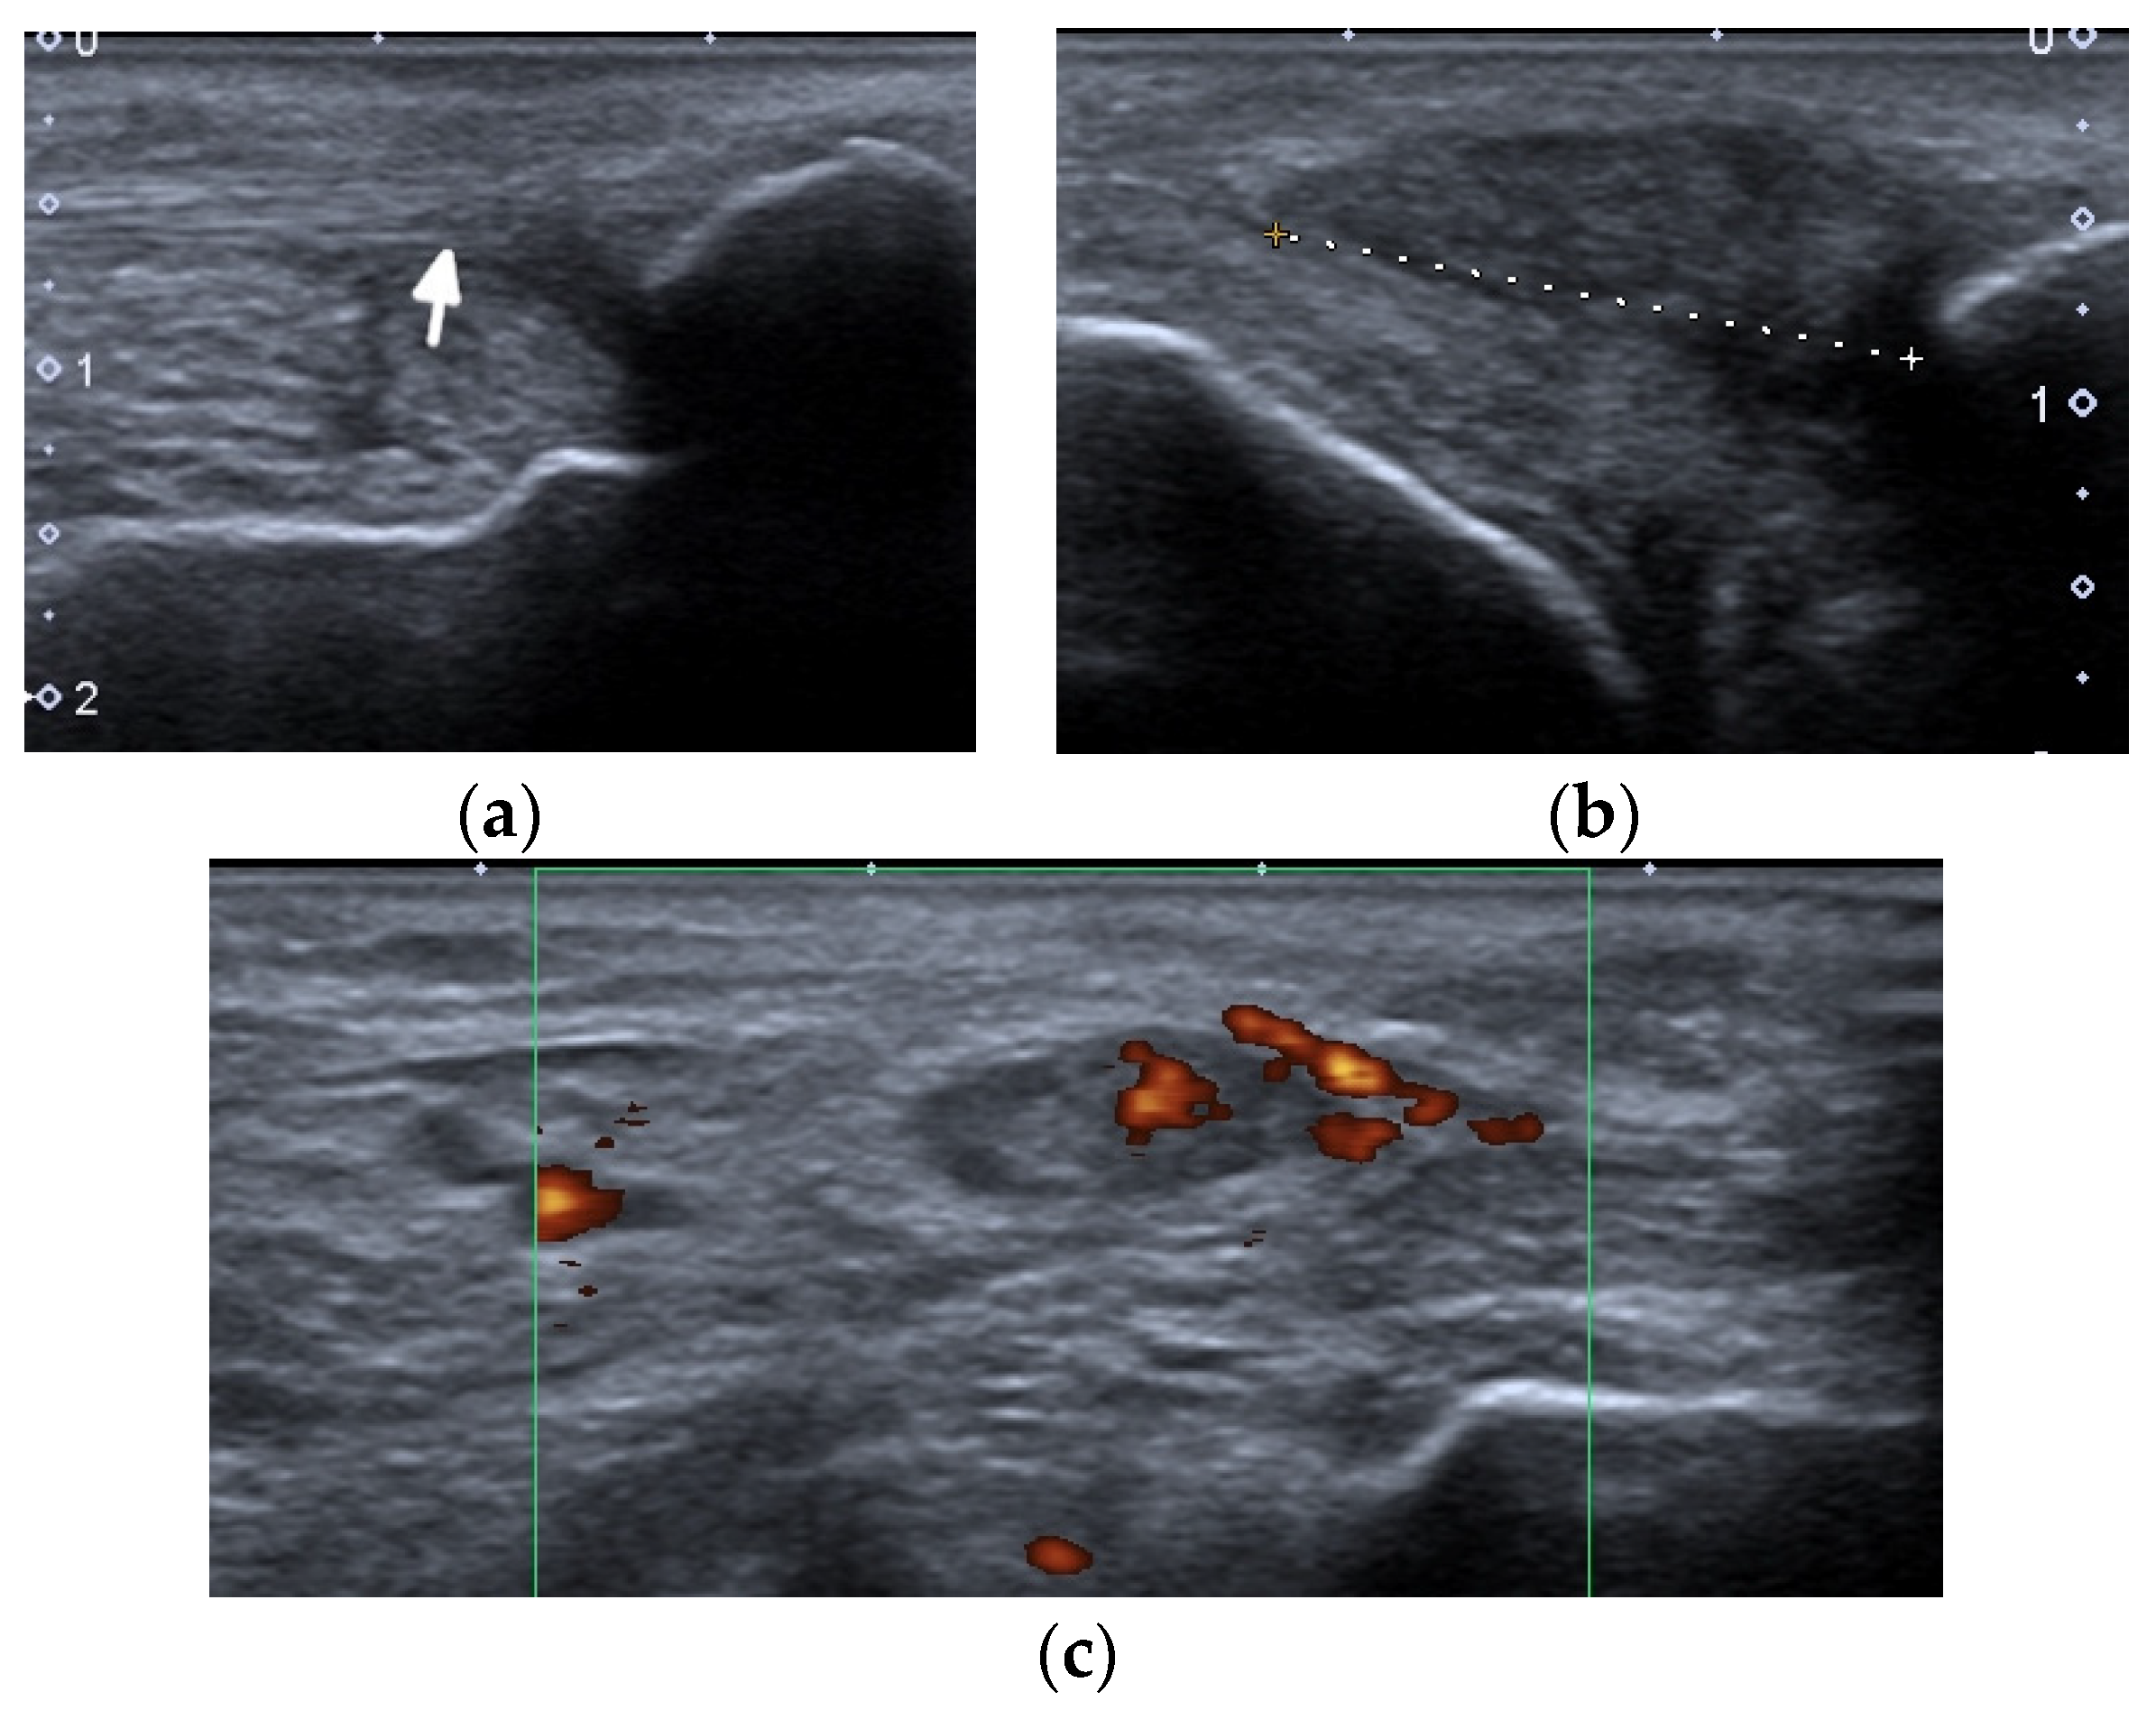

Figure 6.

A complete spontaneous tear of the right posterior tibialis tendon (PTT) 2 cm above the medial malleolus in a 46-year-old female with systemic lupus erythematosus. (a,b) short-axis gray-scale ultrasound (US) images of the medial aspect of the bilateral ankles show the normal echogenic fibrillar appearance of the healthy left PTT (a, arrow) compared to an enlarged, torn right hypoechoic PTT in the same region between calipers in (b). (c) Short-axis power Doppler US image of the affected right side shows hyperemia in the PTT tendon stump, with additional hyperemia in the tendon sheath consistent with tendinopathy and tenosynovitis. Two tiny red dots at the periphery of green Doppler box represent normal vessels.